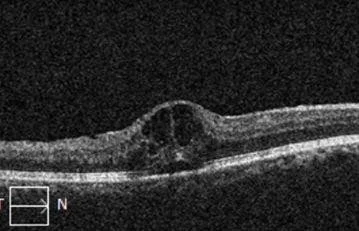

Optical coherence tomography (OCT) images showing macular edema in a patient with retinal vein occlusion.

Top image: An optical coherence tomography (OCT) scan is a safe and painless imaging test that allows for examination of microscopic changes in the retina. Bottom left image: Right eye retina. Left image: OCT-scan through a single slice of the retina shown in the left image. The OCT is normal. The downward dip in the retina is the normal foveal depression.